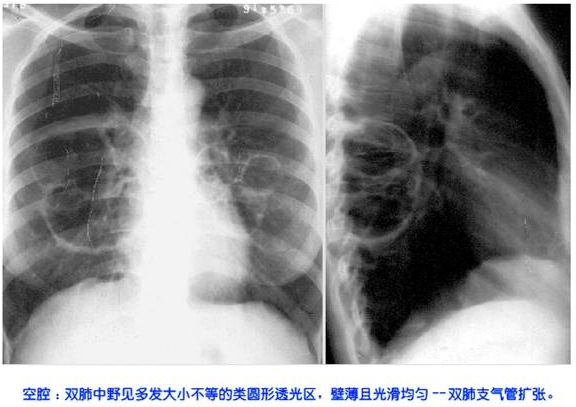

照片名称:空腔